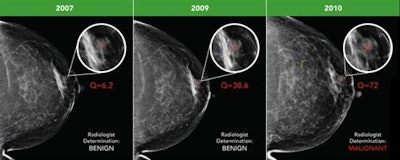

By enabling the objective assessment of any changes seen on sequential mammograms, the software's quantitative scoring may also enhance radiologists' accuracy, she said.

Early breast cancer was flagged by the CAD software three years prior to biopsy and showed a progressive increase in quantitative score over the three years. All images courtesy of Dr. Alyssa Watanabe.

Early breast cancer was flagged by the CAD software three years prior to biopsy and showed a progressive increase in quantitative score over the three years. All images courtesy of Dr. Alyssa Watanabe.In other results, the researchers found that progressive deep-learning training continued to improve the performance of the CAD software over time for breast masses.